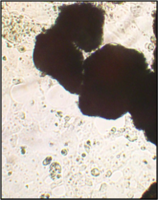

Образец исследуемого материала - кусочек недеминерализованной спонгиозы серии «Лиопласт»® объемом 125 куб. мм (рис. 31) помещали на равномерный монослой фибробластов плотностью 332 клетки/ммІ.

Этот материал имеет нейтральную реакцию (рН=7,2). Так как рН ростовой среды также 7,2-7,3, внесение образца не изменяет реакцию.

Рис. 31. Недеминерализованная спонгиоза серии «Лиопласт»®.